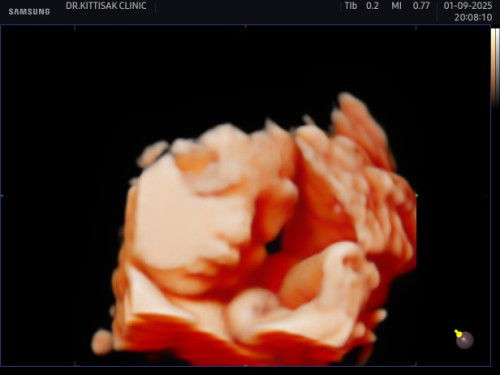

สรุปแล้ว หนูเป็นผู้หญิงค่า🥰

ไปอัลตร้าซาวด์แบบ 4 มิติมาแค่ 200 อึ้งมาก แนะนำคุณแม่เก็บช่วงเวลาดีๆกับคุณพ่อ โดยการพากันไปอัลตร้าซาวด์แบบ 4 มิติดูนะคะ มีความสุขมาก